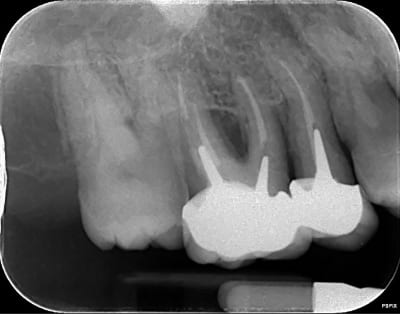

La pano c'est effectivement la xmind trium de acteon

la retro c'est aussi de chez acteon, le pspix2, les erlm sont de chez eux. Que reprochez vous ? Image trop flou ? Vraiment bcp plus flou que chez un concurrent ? Pensez vous que cela vienne des capteurs ou de la machine avec un mauvais reglage de netteté, ou un mauvais réglage tension, intensité,temps exposition ?

Pour les rétro je trouve qu'elles sont pas nettes... moins nettes que la pano.

Peut être que c'est le filtre quand tu exportes les clichés.